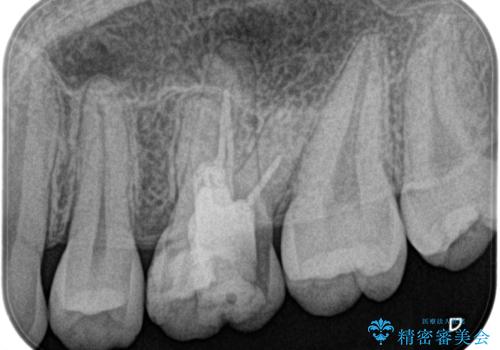

再根管治療後、歯周外科を行い、オールセラミッククラウンにて修復処置を行っております。

根管治療を行った大臼歯は速やかに被せ物の治療を行うことが必要です。

- 根管治療により痛みや腫れがひかない事や、術後に痛みや腫れが生じる事、治療によるファイル破折やパーフォレーションなどの偶発症、術後の歯根破折を生じる可能性もあります